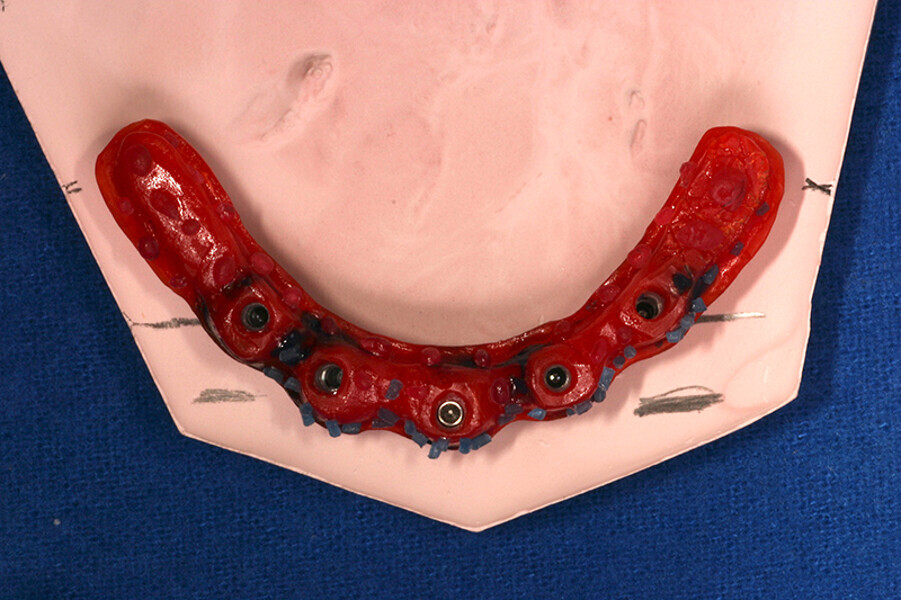

Fig. 4 Prótesis Híbrida inmediata y radiografía control con 6 años post-operatorio